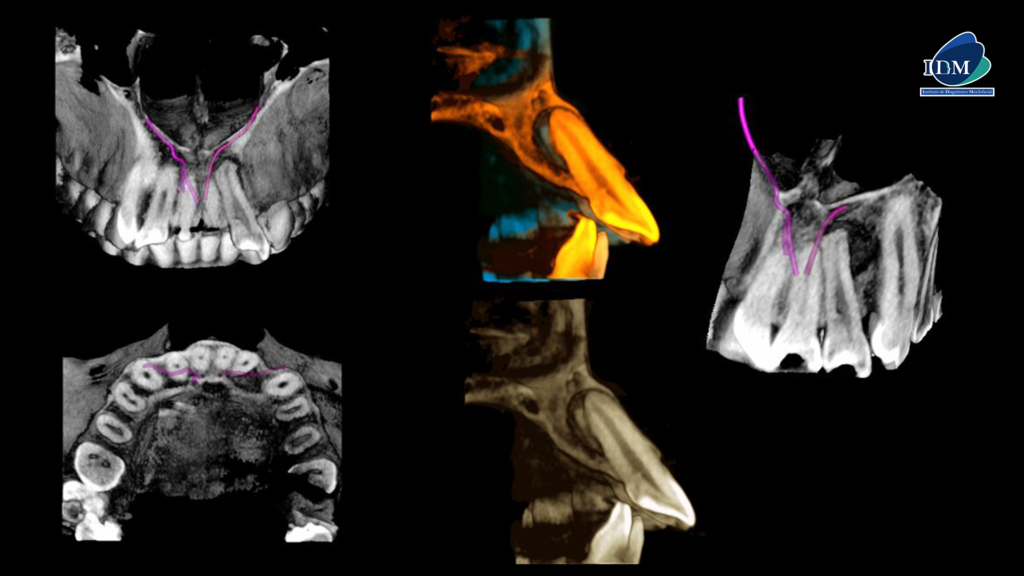

A la evaluación de la tomografía computarizada en los cortes axiales se observan tres hallazgos importantes; primero, la presencia de una imagen hipodensa puntiforme que nace desde el conducto pulpar hasta la cara palatina (flecha amarilla), un proceso osteolítico periapical de la pieza 22 (flecha azul) de forma redondeada que compromete la superficie mesial de la pieza 23 y ocasiona el adelgazamiento de la cortical vestibular, así como el aumento de la densidad ósea circundante compatible con quiste radicular y la presencia de un canalisis sinuosus que se extiende por palatino de la pieza 22 (flecha fucsia).

A la evaluación de los cortes transaxiales y tangenciales se observa la discreta invaginación de la pieza 22 (flecha naranja), así como el recorrido del canalisis sinuosus (flecha verde) y la presencia de la lesión osteolítico próxima a este.

En la reconstrucción 3D se observa de manera más gráfica y además se confirma la presencia de un canal accesorio que nace del canal sinuoso del lado derecho.